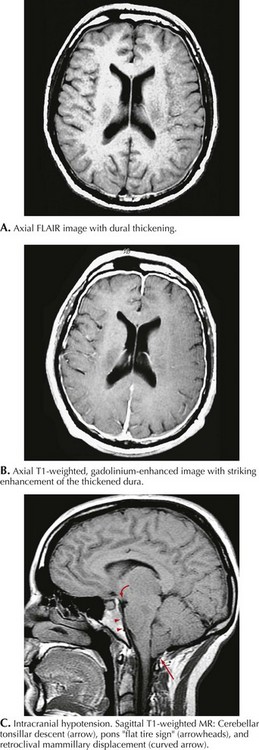

MRI with gadolinium demonstrates diffuse pachymeningeal enhancement in most low–CSF pressure headaches. This is often accompanied by dural thickening that can be striking and may be confused with leptomeningeal inflammatory or neoplastic processes (Fig. 11-9). In more severe cases, subdural fluid collections and descent of the brain with downward displacement of the cerebellar tonsils can be seen. Lumbar puncture demonstrates decreased intracranial pressure, usually less than 50 mm H2O. CSF analysis may be normal, but slight elevation of protein and a mild lymphocytic pleocytosis may be seen. Radioisotope cisternography or contrast myelography can be used to detect sites of CSF leakage.